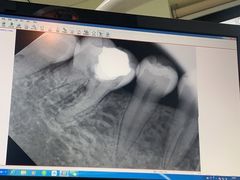

• 松柏口腔门诊

• -松柏口腔门诊

momo | 20-11-13